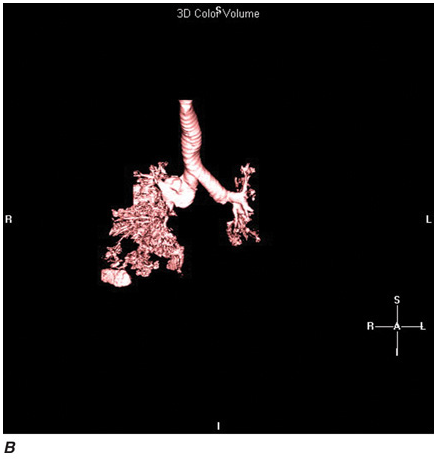

Helical CT Scanning

Recent advances in computer processing have allowed the development of helical CT scanning. Helical CT technology results in faster scans with improved contrast enhancement and thinner collimation. The image is obtained during a single breath-holding maneuver that allows less motion artifact. In addition, helical CT scanning allows the collection of continuous data over a larger volume of lung than is possible with conventional CT. Data from the imaging procedure can be reconstructed as images in planes other than the traditional cross-sectional (axial) view, including coronal, or sagittal planes (Fig. C-3A). Finally, sophisticated volumetric “3D” representations of structures can be produced (Fig. C-3B) including the ability to perform a virtual bronchoscopy, mimicking direct visualization through a bronchoscope (Fig. C-4).

Multidetector CT (MDCT)

Refinements in detector technology have allowed production of scanners with additional detectors along the scanning axis (z-axis). These scanners, called multidetector CT (MDCT) scanners, can obtain multiple slices in a single rotation that are thinner and can be acquired in a shorter period of time. This results in enhanced resolution and increased image reconstruction ability. As the technology has progressed, higher numbers (2, 4, 6, 8, 10, 16, 32, 40 and currently up to 64) of detectors are used to produce clearer final images. The development of MDCT allows for even shorter breath holds, which are beneficial for all patients but especially children, the elderly, and the critically ill. However, it should be noted that despite the advantages of MDCT, there is an increase in radiation dose compared to single-detector CT to consider. With MDCT, the additional detectors along the z-axis result in improved use of the contrast bolus. In addition, the shorter breath holds secondary to faster scanning times and increased resolution have all led to improved imaging of the pulmonary vasculature and the ability to detect segmental and subsegmental emboli. In contrast to pulmonary angiography, CT pulmonary angiography (CTPA) also allows simultaneous detection of parenchymal abnormalities that may be contributing to a patient’s clinical presentation. Secondary to these advantages and increasing availability, CTPA has rapidly become the test of choice for many clinicians in the evaluation of pulmonary embolism; it is considered equal to pulmonary angiography in terms of accuracy, and with less associated risks.